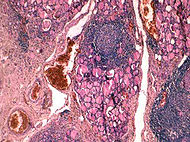

Зоб Хошимото ( Хошимото-японский врач, впервые описавший данный вид зоба) - увеличение щитовидной железы с диагносцированными критериями аутоиммунного тиреоидита.

Болезнь Хасимото — аутоиммунный тиреоидит (воспаление щитовидной железы), начинается обычно в детстве, часто прогрессирует до полного отказа железы в среднем возрасте. Чаще встречается у женщин. Лечение — восполнение тироксина (щитовидного гормона). При своевременном лечении прогноз благоприятный.